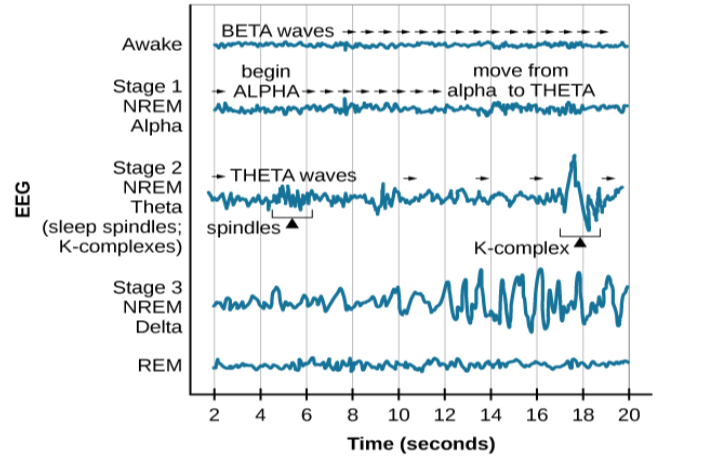

Sleep is not a uniform state of being. Instead, sleep is composed of several different stages that can be differentiated from one another by the patterns of brain wave activity that occur during each stage. These changes in brain wave activity can be visualized using EEG and are distinguished from one another by both the frequency and amplitude of brain waves (Figure 4.7). Sleep can be divided into two different general phases: REM sleep and non-REM (NREM) sleep. Rapid eye movement (REM) sleep is characterized by darting movements of the eyes under closed eyelids. Brain waves during REM sleep appear very similar to brain waves during wakefulness. In contrast, non-REM (NREM) sleep is subdivided into four stages distinguished from each other and from wakefulness by characteristic patterns of brain waves. The first three stages of sleep are NREM sleep, while the fourth and final stage of sleep is REM sleep. In this section, we will discuss each of these stages of sleep and their associated patterns of brain wave activity.

The first stage of NREM sleep is known as stage 1 sleep. Stage 1 sleep is a transitional phase that occurs between wakefulness and sleep, the period during which we drift off to sleep. During this time, there is a slowdown in both the rates of respiration and heartbeat. In addition, stage 1 sleep involves a marked decrease in both overall muscle tension and core body temperature.

In terms of brain wave activity, stage 1 sleep is associated with both alpha and theta waves. The early portion of stage 1 sleep produces alpha waves, which are relatively low frequency (8–13Hz), high amplitude patterns of electrical activity (waves) that become synchronized (Figure 4.8). This pattern of brain wave activity resembles that of someone who is very relaxed, yet awake. As an individual continues through stage 1 sleep, there is an increase in theta wave activity. Theta waves are even lower frequency (4–7 Hz), higher amplitude brain waves than alpha waves. It is relatively easy to wake someone from stage 1 sleep; in fact, people often report that they have not been asleep if they are awoken during stage 1 sleep.

As mentioned earlier, REM sleep is marked by rapid movements of the eyes. The brain waves associated with this stage of sleep are very similar to those observed when a person is awake, as shown in Figure 4.11, and this is the period of sleep in which dreaming occurs. It is also associated with paralysis of muscle systems in the body with the exception of those that make circulation and respiration possible. Therefore, no movement of voluntary muscles occurs during REM sleep in a normal individual; REM sleep is often referred to as paradoxical sleep because of this combination of high brain activity and lack of muscle tone. Like NREM sleep, REM has been implicated in various aspects of learning and memory (Wagner, Gais, & Born, 2001; Siegel, 2001).

The different stages of sleep are characterized by the patterns of brain waves associated with each stage. As a person transitions from being awake to falling asleep, alpha waves are replaced by theta waves. Sleep spindles and K-complexes emerge in stage 2 sleep. Stage 3 and stage 4 are described as slow-wave sleep that is marked by a predominance of delta waves. REM sleep involves rapid movements of the eyes, paralysis of voluntary muscles, and dreaming. Both NREM and REM sleep appear to play important roles in learning and memory. Dreams may represent life events that are important to the dreamer. Alternatively, dreaming may represent a state of protoconsciousness, or a virtual reality, in the mind that helps a person during consciousness.